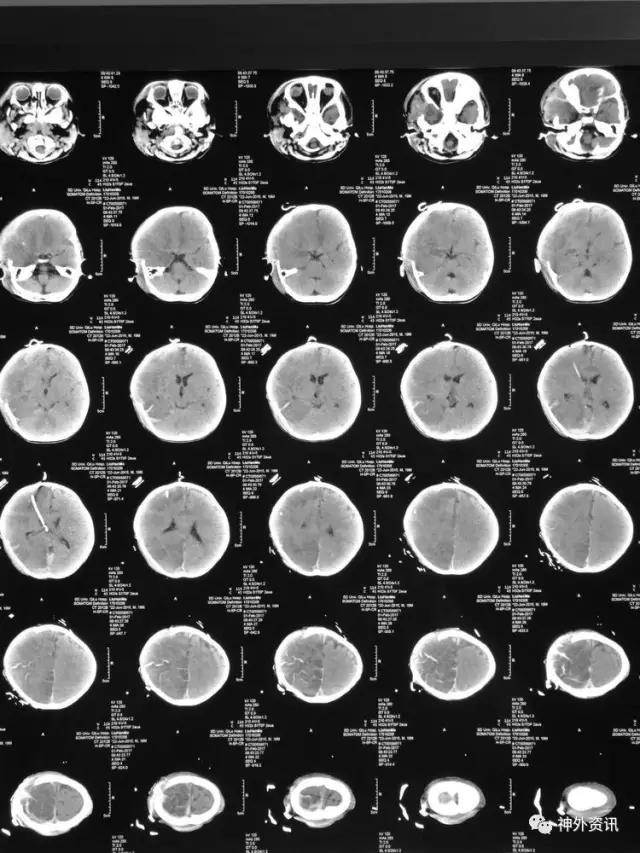

患儿刘**,男,19个月,2017.1.30 2pm不慎摔倒,意识障碍,刺痛不睁眼,不发音,刺痛肢体屈曲,急至当地医院,伤后1小时颅脑CT结果示右额颞顶枕急性硬膜下血肿,中线轻微左移:

3小时后转至我院急诊科,当时查体:刺痛不睁眼,不发音,刺痛右侧肢体屈曲,右侧瞳孔5mm,对光反应消失,左侧瞳孔0.3cm,对光反应迟钝,立即术前准备并复查CT,结果示右额颞顶枕硬膜下血肿,右侧大脑半球及左侧额叶弥漫性低密度,考虑缺血,中线左移明显,脑沟及环池显示不清:

术后移动CT结果示中线移位较术前减轻,顶枕部蛛网膜下腔出血:

2017.2.1:术后2天复查颅脑CT,结果示中线居中,右侧半球低密度并SAH,左侧半球未见明显异常,左侧脑沟可见显示,双肺少量炎症,不能放松警惕,继续同前治疗。

2017.2.4:术后5天复查颅脑CT,结果示中线居中,左侧半球及环池显示清晰,右侧半球脑沟显示欠清晰,脑组织低密度较前有所好转,继续同前治疗。已加用预消化肠内营养液及促进胃肠动力药物。

2017.2.6:术后7天,复查颅脑CT示情况较前进一步好转,逐步撤掉冰毯,缓慢自然复温。

2017.2.8:术后9天,复查颅脑及胸部CT,结果显示双侧脑沟脑回及环池显示清晰。颅压控制,拔除引流管探头,头部敷料稍加压包扎,此时已更替力月西为丙泊酚,停用呼吸机。